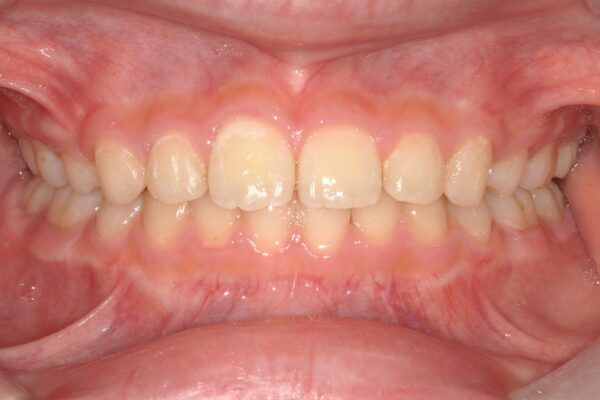

⑤装置除去(1年9か月後)

当初、歯の移動量が多いことから2年前後の期間を予定していましたが、結果として1年9か月という、予定よりも早い期間で装置を外すことができました。

【治療結果】

・著大だったオーバージェット(前歯の突出)が完全に解消され、良好な被蓋関係(咬み合わせ)を獲得しました。

・突出していた口元が下がり、バランスの取れた良好な側貌(横顔)が得られました。

・スペース不足で生えてこなかった下顎の7番も、正常な位置へと誘導することができました。